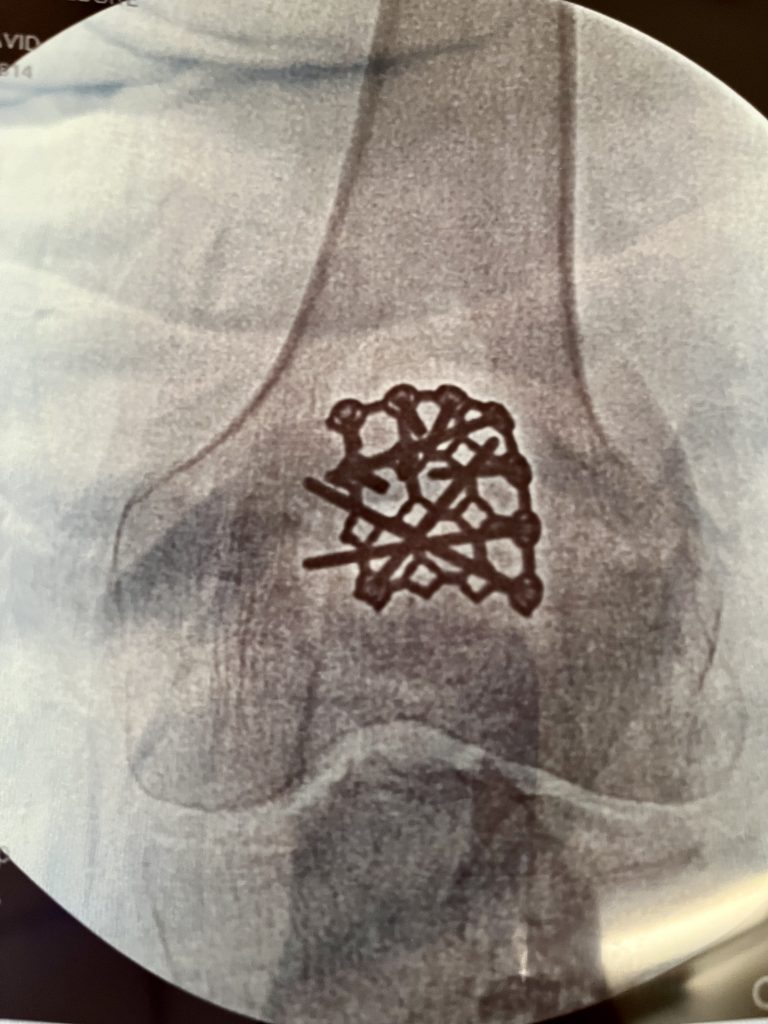

My leg continues to swell, and Dr. David Helfet had looked at my leg, and immediately rushed me to the OR did a 4 compartment release saving my only leg... I was discharged after 8 days, but had an issue where my local ER Took my pressures which showed they were 85... I went against local medic advise in CT for fear of getting another infection, and told Dr. Helfet's PA's I would get down there first thing in the am. Once again, he opened all of my compartments to avoid the extensive swelling to keep happening. I have had 5 surgeries since April 12, thru present time. Yesterday I had Dr. Helfet do a final dentredment and Dr. Gayle did a flap/skin graft... The care here is outstanding.